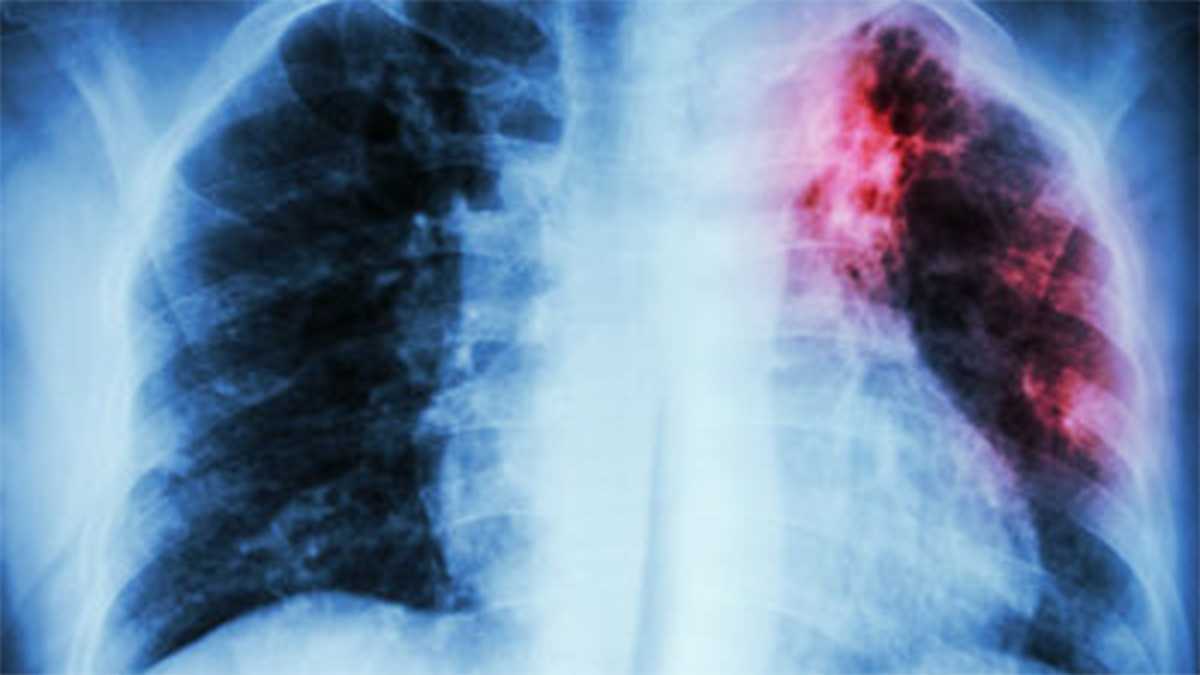

New Hampshire health officials identified two additional active tuberculosis cases infectious in Manchester and Nashua, bringing the total to three cases in the state since March. The Department of Health and Human Services is working with Manchester and Nashua health departments and community partners to identify and notify possible contacts but warned that exposures at several public locations may make it impossible to reach everyone. Officials are asking anyone who attended the “Loads of Love” event at Wash Street Laundromat (1231 Elm St.) on Jan. 1–July 17 (Monday and Thursday nights, 10 p.m.–1 a.m.) or who was at the Hillsborough County Department of Corrections (445 Willow St.) April 16–25 or May 9–Aug. 15 to seek TB testing; an earlier case involved the Families in Transition shelter and the 12-69 Cafe where outreach clinics were held. Free testing is available through local public health departments (for example the Nashua Division of Public Health and the Manchester Health Department) and people without a primary care provider can call 2-1-1 for help accessing care. Deputy State Epidemiologist Dr. Elizabeth Talbot said the overall risk of becoming sick after exposure is low but screening can prevent serious illness and further spread; residents should watch for symptoms such as a persistent cough, unexplained weight loss, night sweats and fever, and note that latent TB infection can require treatment even if no symptoms are present.